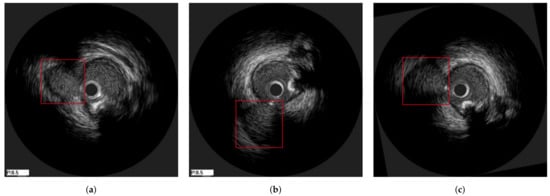

3.3. Axial Registration

- Rigid distortion, by randomly translating and rotating an image to simulate the circumferential movement of the probe. The rotation range was , the translation range is pixels and both are sampled based on the uniform distribution.